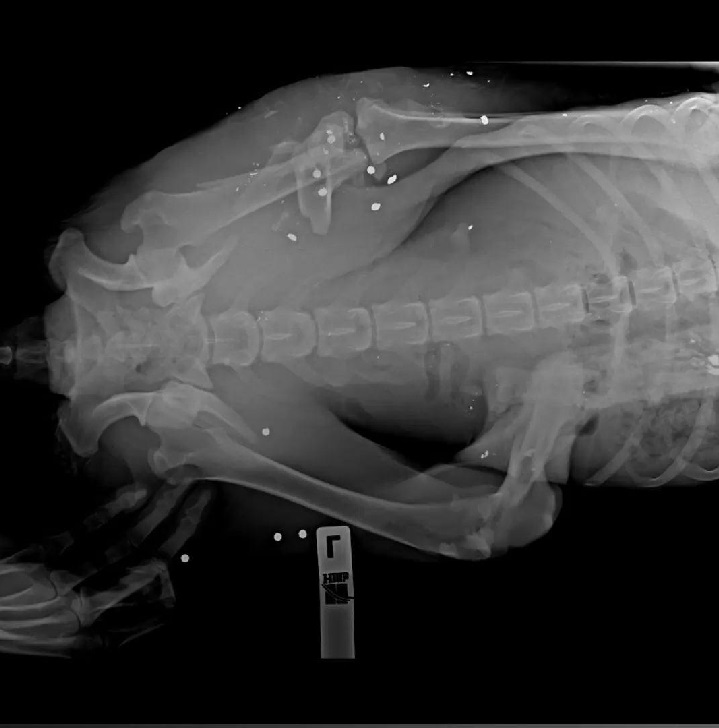

В Алексеевке под Уфой живодёры расстреляли собаку из дробовика. Снаряды перебили ей обе задние лапы, а дробь прошила всё тело, включая позвоночник. Чудом Афина выжила. Она ползла на передних лапах и добралась до людей, которые, не остались равнодушными нашли волонтёров и отправили её в ветклинику.

Два года спустя Афина всё ещё борется за свою жизнь. После двух тяжёлых операций она смогла встать на ноги. Задние лапы не восстановились полностью, но она движется и ведёт активную жизнь, несмотря на пережитую боль. За Афиной ухаживают волонтёры, и сейчас она живёт в приюте. Афина стала местной знаменитостью — о ней сняли репортаж на ТВ. Она по-прежнему остаётся добродушной и ласковой. И да, она всё ещё ждёт свою семью. Ищите Афину в «АНО ПОМОЩИ ЖИВОТНЫМ И ПТИЦАМ "НАЙДИ МЕНЯ"».

Афина с трудом выжила благодаря своевременной помощи. Фото: АНО ПОМОЩИ ЖИВОТНЫМ И ПТИЦАМ "НАЙДИ МЕНЯ"